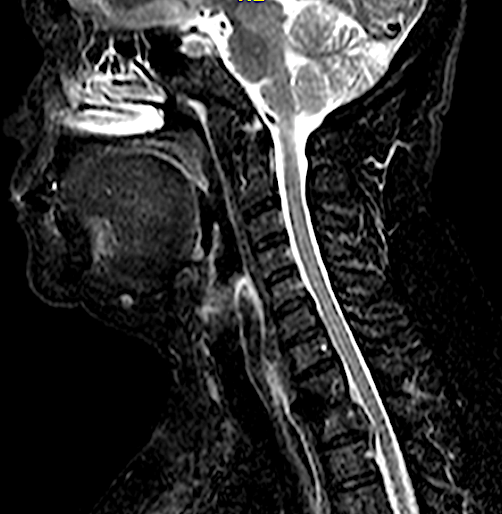

CASO CLÍNICO 2: HERNIA DISCAL C7-TH1 ASOCIADA A ESTENOSIS DE CANAL

Paciente de 46 años que consulta por clínica de mielopatía cervical de evolución progresiva en los últimos dos meses. Tuvo una braquialgia derecha 4 meses antes que mejoró con tratamiento conservador.

Este caso me parece interesante porque hubiese podido ser tratado por vía posterior al ser una hernia lateral, sin embargo, no se trataba de una afectación segmentaria aislada sino que en la misma RM podía apreciarse estenosis de canal en C6-C7 con compresión medular a dicho nivel. No hay que olvidar que el motivo de la consulta fue la instauración de una mielopatía cervical progresiva (inestabilidad, urgencia miccional e hiperreflexia) pues la braquialgia derecha estaba en proceso de remisión.

Por las razones expuestas, a pesar de un thoracic inlet angle bastante alto, opté por realizar un abordaje anterior con descompresión + artrodesis IS con cajas atornilladas C7-Th1.

La evolución clínica fue favorable. En la RX control lateral apenas podemos visualizar la caja inferior sin embargo, por la ausencia de dolor, por la falta de edema en STIR en cuerpos vertebrales C7-Th1 y por la resolución de la clínica neurológica no considero imprescindible por ahora, someter al paciente a un TC cervical (gran radiación en paciente joven).